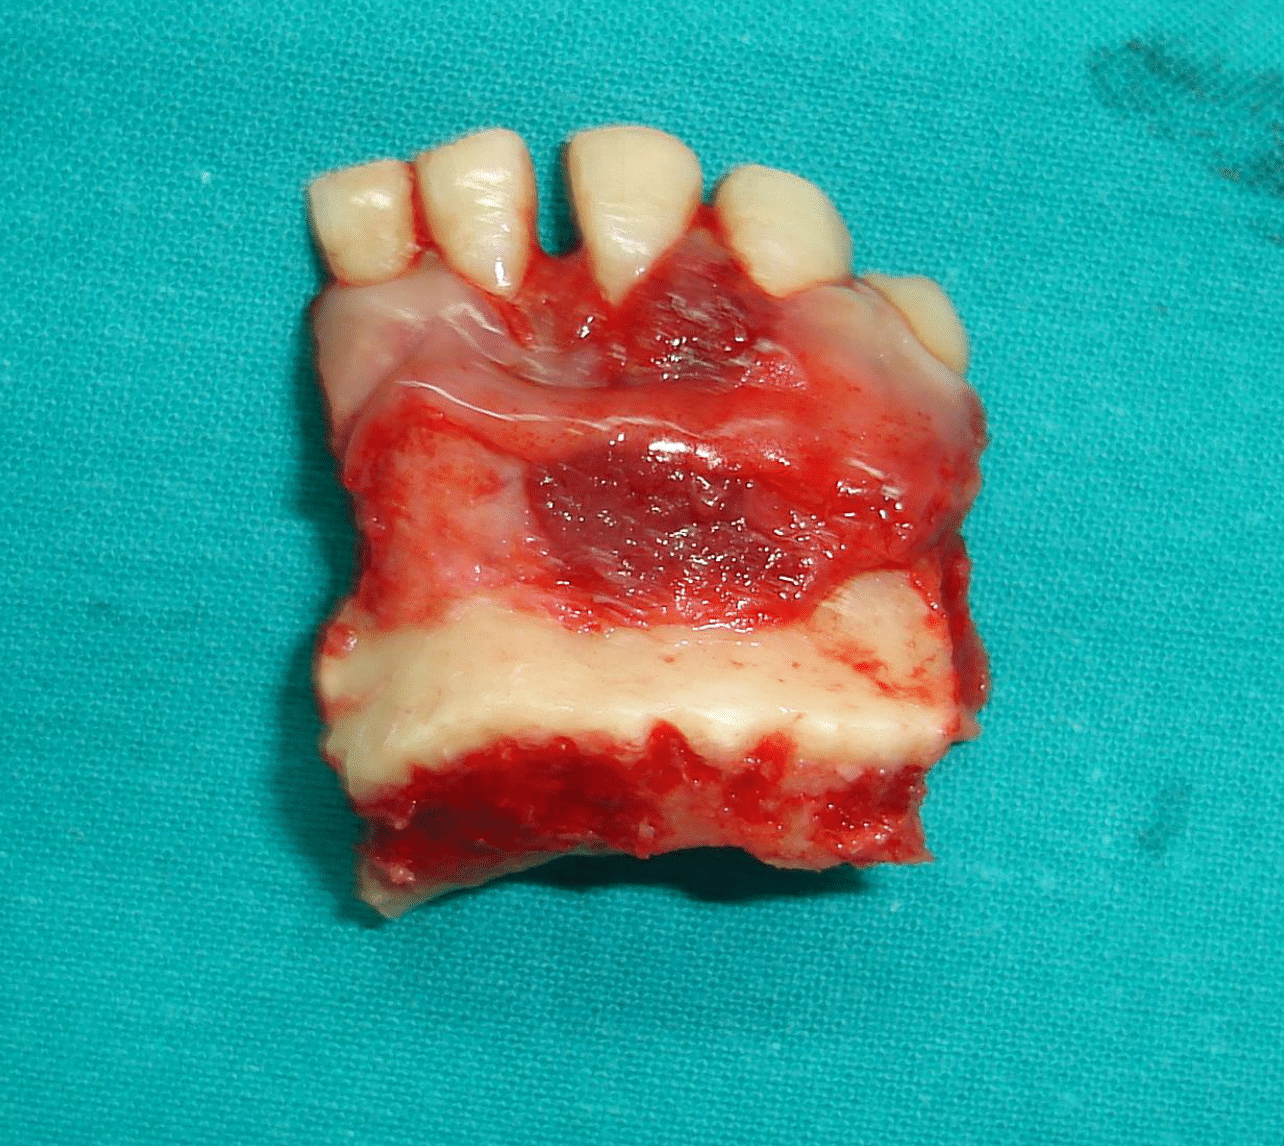

IRB and patient informed consent were obtained. Under general anaesthesia, marginal mandibular resection (alveolar rim resection with preservation of the inferior border) was done with safety margins around all the tissues with clinically evident tumor including the teeth. The safety margin involved the right central and lateral incisors and left canine and first premolar teeth with 0.5 cm of the bone apical to the teeth. A thin osteotome is then used to complete the bony cut through the alveolar process and between the teeth, attempting to maintain the integrity of the soft tissue and avoid damaging teeth. The wound healing was decent, and the soft tissue profile was good (Figure 3A, B, C, and D).

Figure 3a Outline of the mandibular marginal resection with surgical burs.

Figure 3b The resected bony segment.

Figure 3c The mandible after resection of the GSCC.

After resection, the mandible was decalcified and was sectioned to determine bone invasion. Histopathological report suggested that all margins were free and no involvement of mandibular bone.